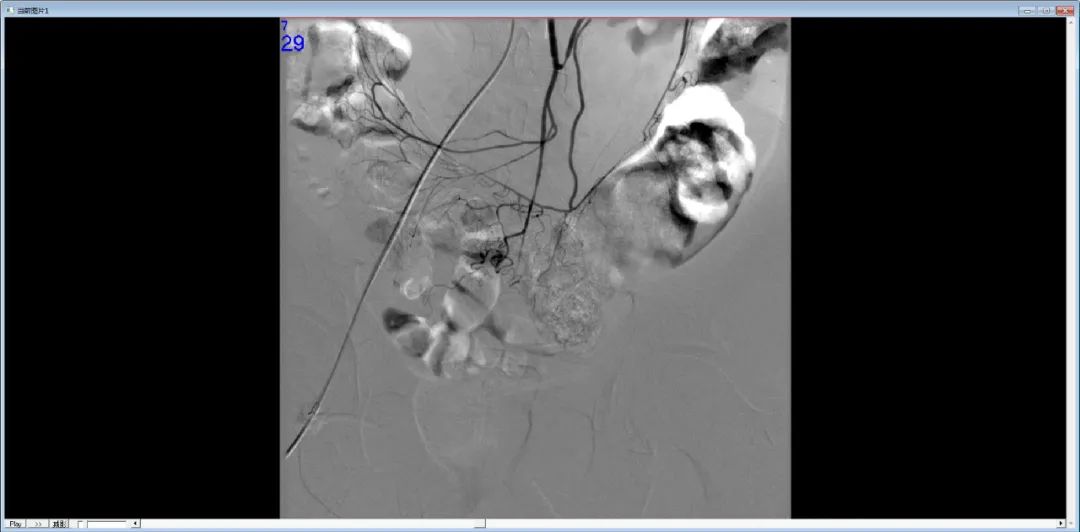

DSA示血管走行中断

DSA示对比剂外溢

栓塞后DSA未见出血征象